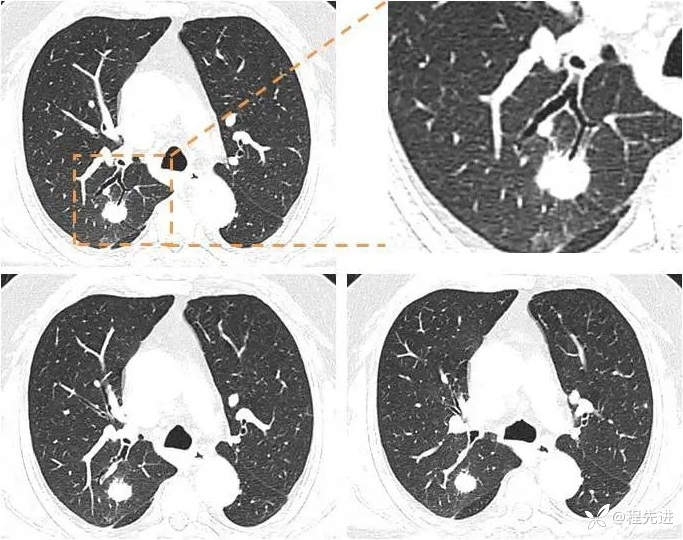

肺窗